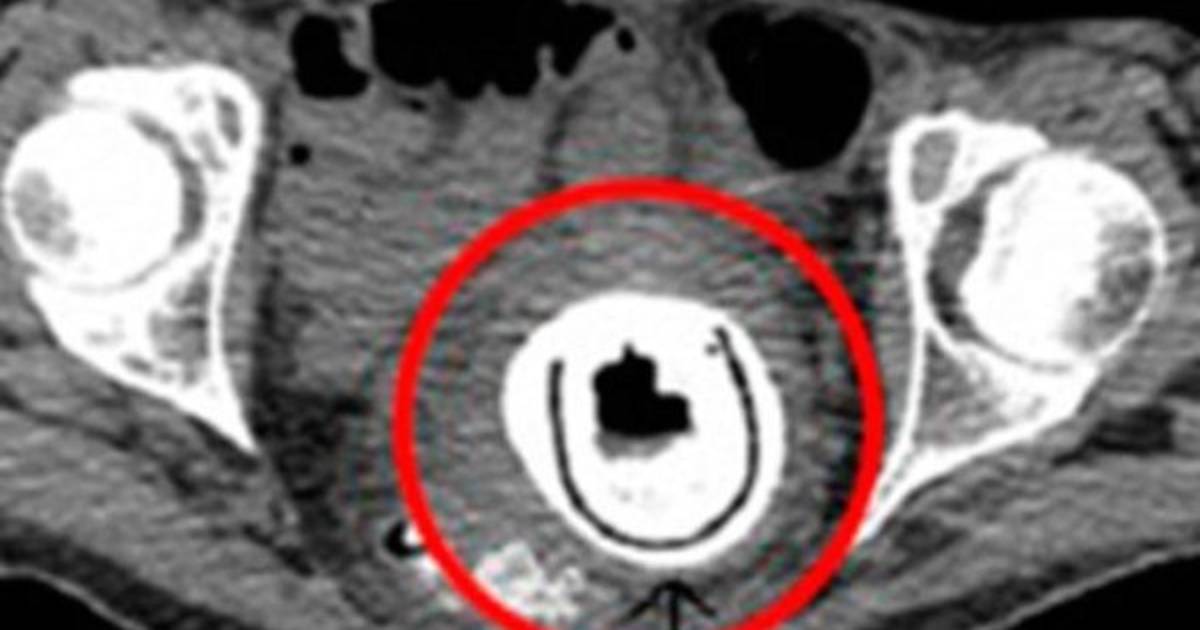

La fémina de 38 años acudió al doctor, quien no podía dar crédito a la imagen que mostraba la radiografía del abdomen, en la que se apreciaba el juguete sexual incrustado.